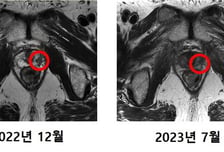

한달만에 암 사라져, 주변 장기 피해 '0'…3000억 들인 '꿈의 치료기' 성공

국내 첫 중입자치료를 받은 전립선암(전립샘암) 환자의 치료 결과가 '성공적'인 것으로 확인됐다. 연세대의료원 산하 연세암병원은 "전립선암 2기 진단 후 지난 4월 중입자치료를 받은 최 모(64) 씨의 치료 후 검사에서 암 조직이 제거됐다"고 19일 밝혔다. 지난해 건강검진에서 전립선암 의심 소견을 받은 최 씨는 정밀검사를 통해 전립선암 2기로 진단받았다. 최 씨의 '글리슨 점수(Gleason score)'는 3등급이었고, '전립선특이항원(PSA) 수치'는 7.9ng/㎖였다. 글리슨 점수(Gleason score)는 전립선암 악성도를 5등급으로 구분해 평가하는데, 4등급부터 '고위험군'으로 분류한다. 최 씨의 경우 고위험군으로 분류되기 바로 전 단계였다. PSA 검사는 혈액 속 전립선 특이항원 농도를 확인해 전립선암 위험도를 측정하는 검사다. 최 씨는 60대 PSA 정상수치인 4ng/㎖보다 높았다. 지난 4월 말 치료를 시작한 최 씨는 한 주에 3~4회씩 총 12번 치료받아 5월 중순